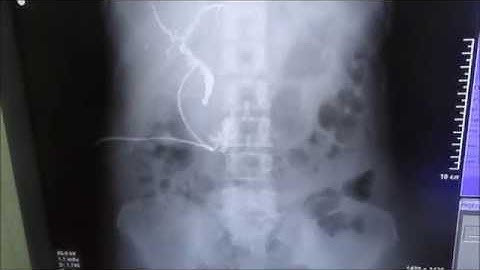

T tube cholangiogram lecture